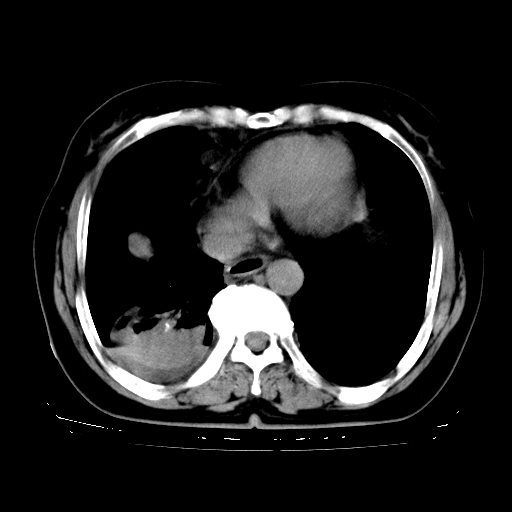

以下是引用zhangzhongshou在2008-3-22 12:52:00的发言:[br]1、右侧液气胸。[br]2、腹水。建议进一步检查。

以下是引用鲁巨ct在2008-3-22 14:10:00的发言:[br]1、右侧液气胸,右中下叶节段性不张。[br]2、腹水,建议上腹部ct检查

以下是引用zjzjr在2008-3-22 17:19:00的发言:[br]1、右侧液气胸,右下叶节段性不张。[br]2、腹水,建议上腹部ct检查